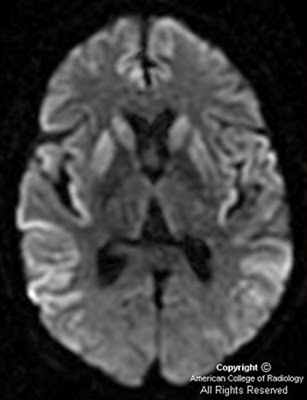

Болезнь Крейтцфельда–Якоба (БКЯ) является редким нейродегенеративным заболеванием, обусловленным накоплением патологической изоформы прионного белка. Классическая клиническая картина БКЯ характеризуется быстро прогрессирующей деменцией, атаксией, миоклонией, а также акинетическим мутизмом в терминальной стадии заболевания. Из инструментальных методов исследования ведущая роль в клинической практике принадлежит магнитно-резонансной томографии головного мозга. С 2014 по 2019 г. в Республике Саха (Якутия) авторы наблюдали 4 пациентов с вероятной БКЯ. У всех пациентов были примерно одинаковые возраст дебюта заболевания (50–60 лет) и начало с неспецифических церебральных симптомов. Однако последующее развитие быстро прогрессирующей деменции и других характерных признаков позволило предположить БКЯ. У пациентов выявлены показательные нейровизуализационные признаки в виде гиперинтенсивности хвостатых ядер и подушек таламуса в режимах FLAIR и DWI с образованием типичного сигнала «хоккейных клюшек», а также гиперинтенсивность серого вещества в режиме DWI (симптом «ожерелья Венеры»). У 3 пациентов заболевание закончилось фатально в течение года после его дебюта. Четвертая пациентка находится под домашним наблюдением (длительность заболевания 6 мес).

До недавнего времени «золотым стандартом» верификации диагноза БКЯ являлась биопсия головного мозга, позволяющая выявить характерные изменения в мозговой ткани в виде мелких вакуолей в телах нейронов, из-за чего ткань мозга приобретает губчатый вид, пролиферации клеток глии при отсутствии признаков воспаления. При электронной микроскопии возможно обнаружение прионных палочек, являющихся патогномоничным признаком заболевания. Указанные морфологические изменения отмечаются в коре головного мозга, базальных ганглиях, мозжечке и верхних отделах ствола мозга. Однако в случаях БКЯ биопсия мозга не нашла широкого применения в клинической практике из-за инвазивности метода, сложности санитарной обработки оборудования и утилизации биоматериалов, связанных с высокой устойчивостью прионов, а также вследствие небольшого объема биоптата мозговой ткани, что может быть причиной ложноотрицательных результатов морфологического и иммуногистохимического исследования. Однако в настоящее все больше распространена МРТ диагностика данного заболевания, по причине выявления специфических изменений, наиболее информативными являются последовательность DWI.

Магнитно-резонансная томография позволяет получить качественные и контрастные изображения головного мозга пациента. Во время проведения МРТ выявляются участки повышенного сигнала, локализованные в подкорковых ганглиях и таламусах. Кроме того, магнитно-резонансная томография дает возможность успешно определять признаки атрофических изменений мозжечка, коры головного мозга и расширение желудочковой системы.